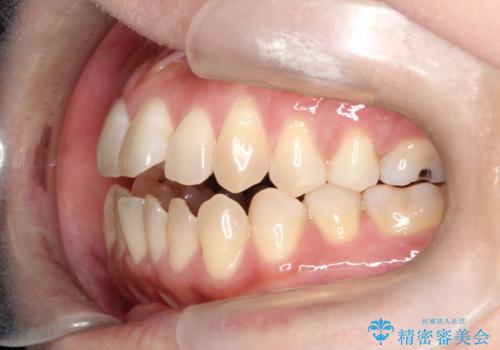

【開咬】笑った時の見た目を改善したい。

- 重度の開咬でしたがインビザラインで適切に治療計画を立て、きれいに仕上がりました。